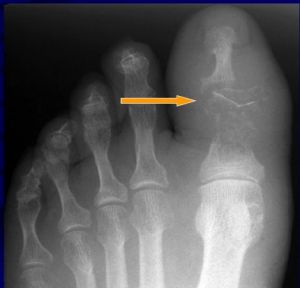

(2)有死骨或彈片等異物和死腔的存在。

6、X射線:骨幹增粗密度大硬化不規則。骨腔變窄或消失、死骨形成等。